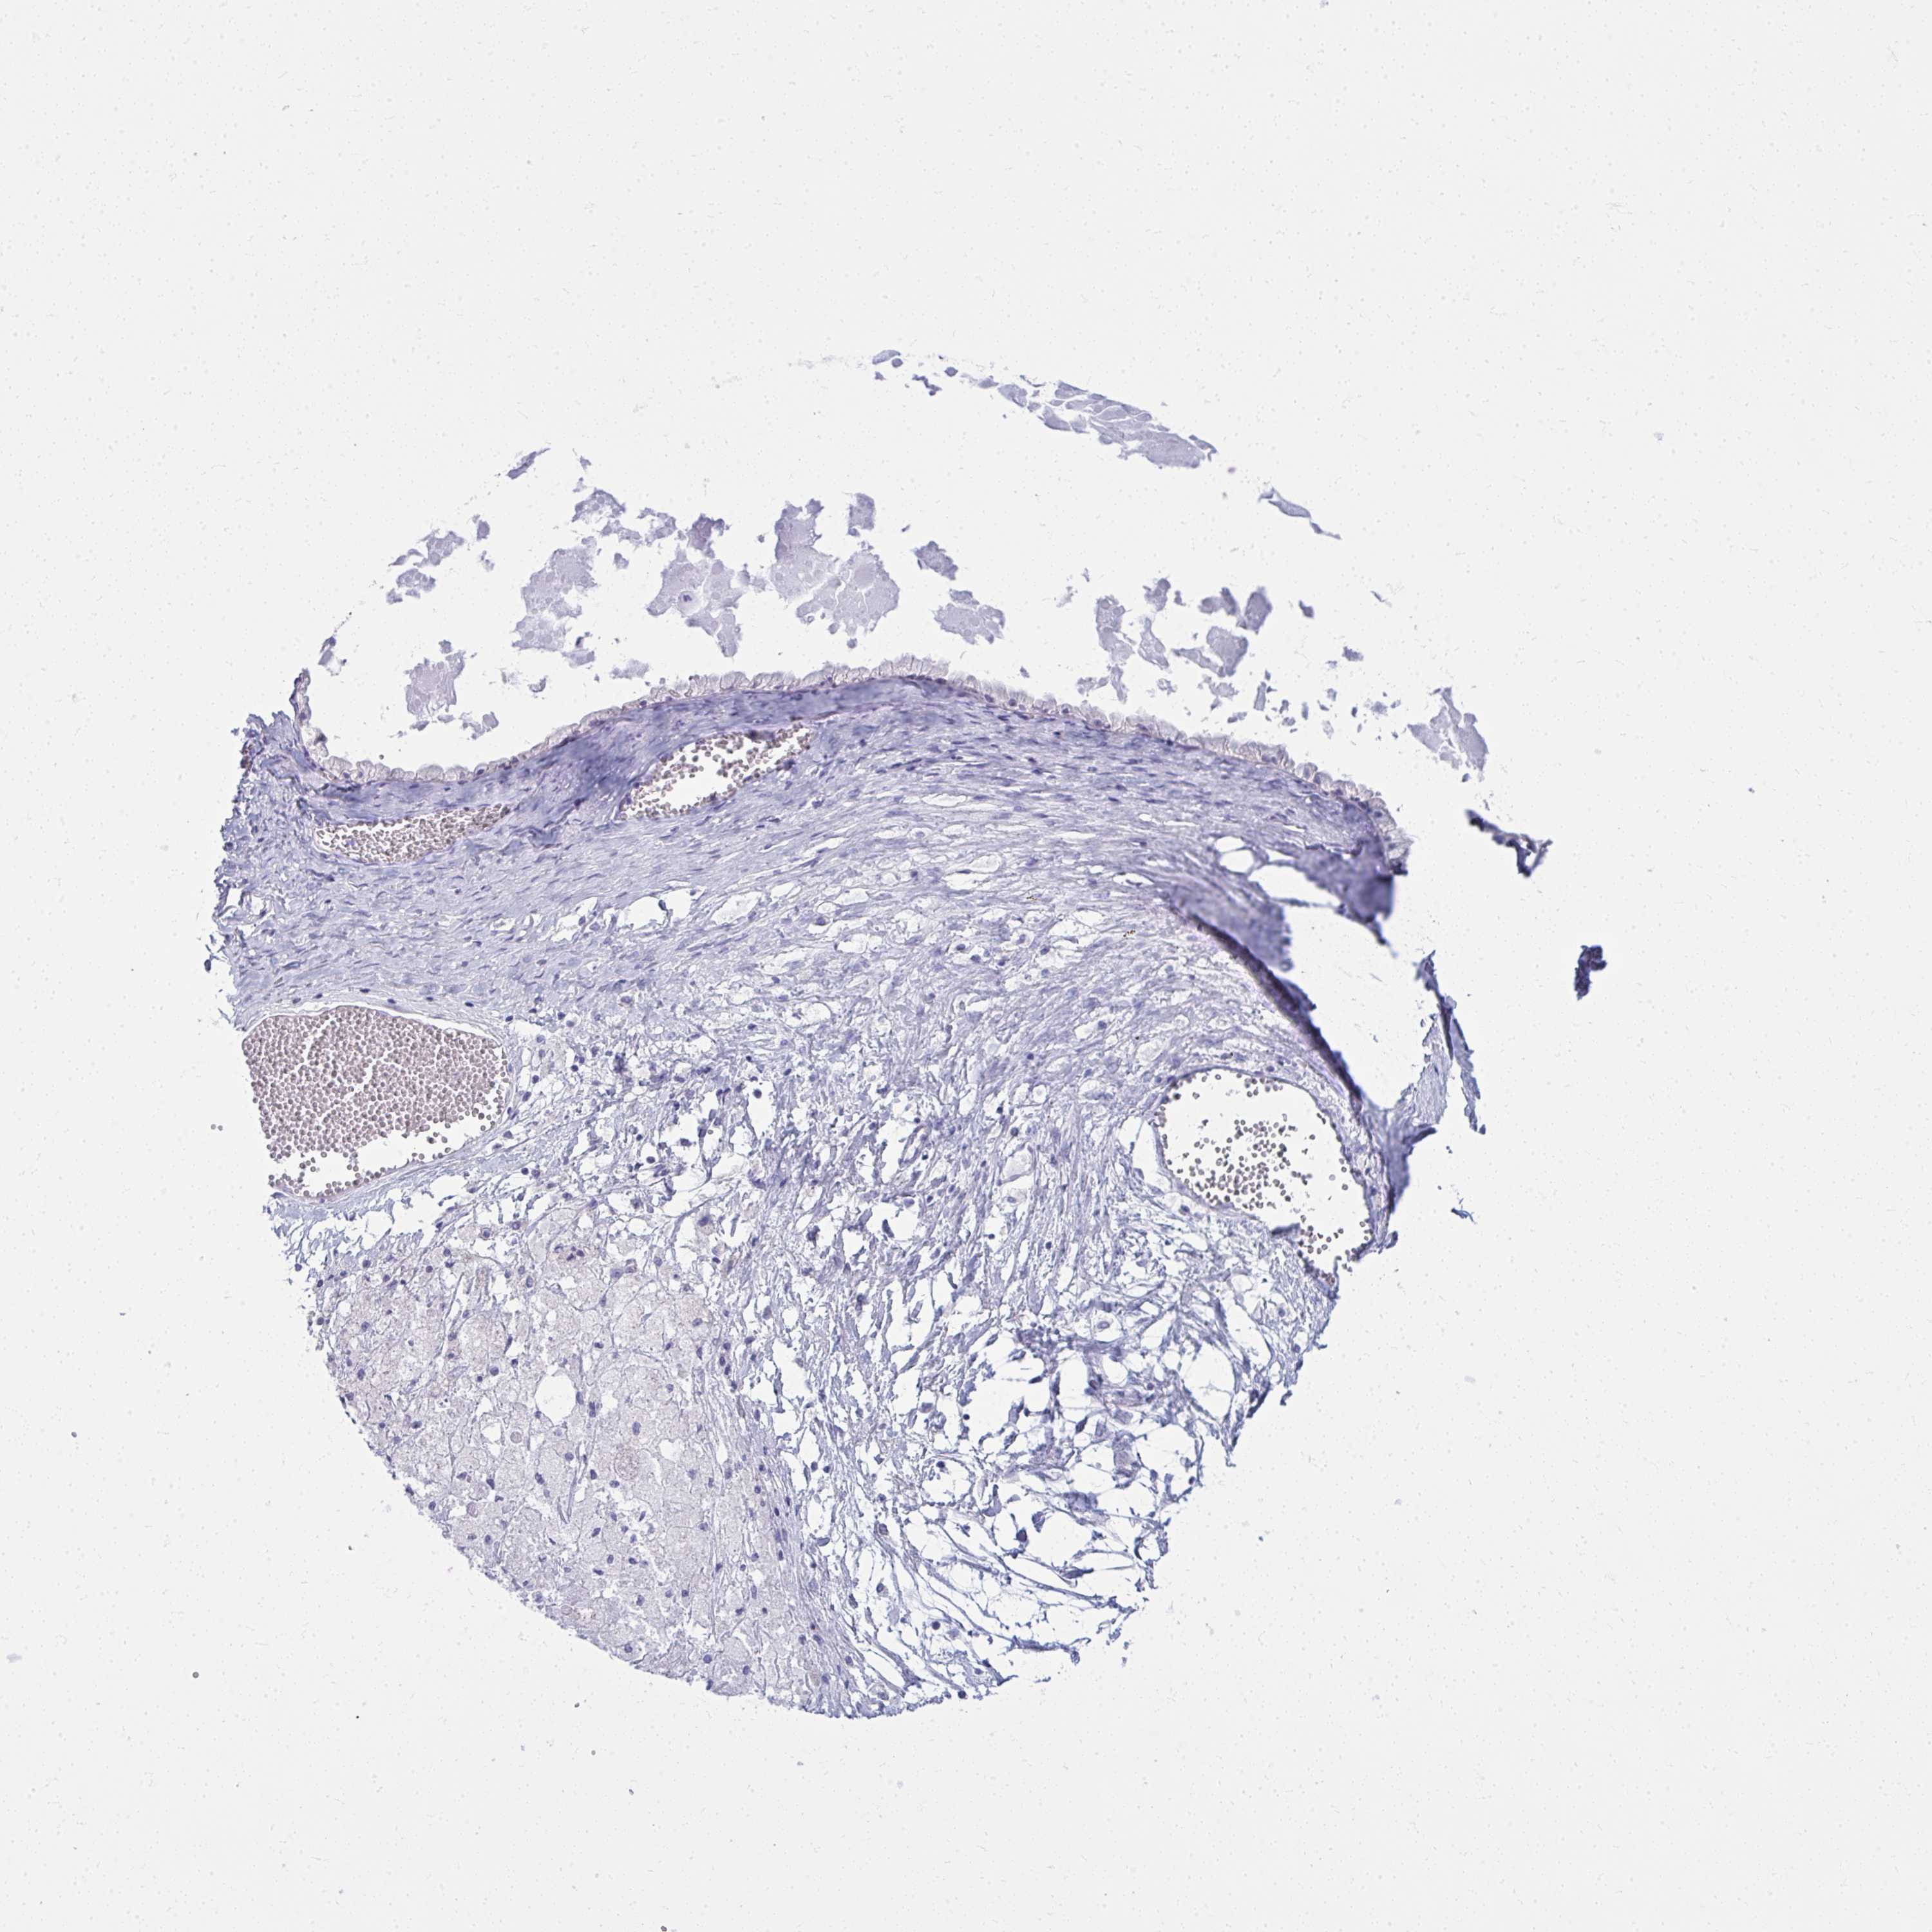

OVARIAN CANCER - Protein expressioni

A mouse-over function shows sample information and annotation data. Click on an image to view it in a full screen mode. Samples can be filtered based on level of antibody staining by selecting one or several of the following categories: high, medium, low and not detected. The assay and annotation is described here.

Note that samples used for immunohistochemistry by the Human Protein Atlas do not correspond to samples in the TCGA dataset.

Antibody stainingi

Antibody staining in the annotated cell types in the current human tissue is reported as not detected, low, medium, or high, based on conventional immunohistochemistry profiling in selected tissues. This score is based on the combination of the staining intensity and fraction of stained cells.

Each image is clickable and will lead to virtual microscopy that enables deeper exploration of all samples and also displays staining intensity scores, fraction scores and subcellular localization as well as patient and tissue information for each sample.

Antibody HPA058951

Cystadenocarcinoma, serous, NOS

Carcinoma, NOS